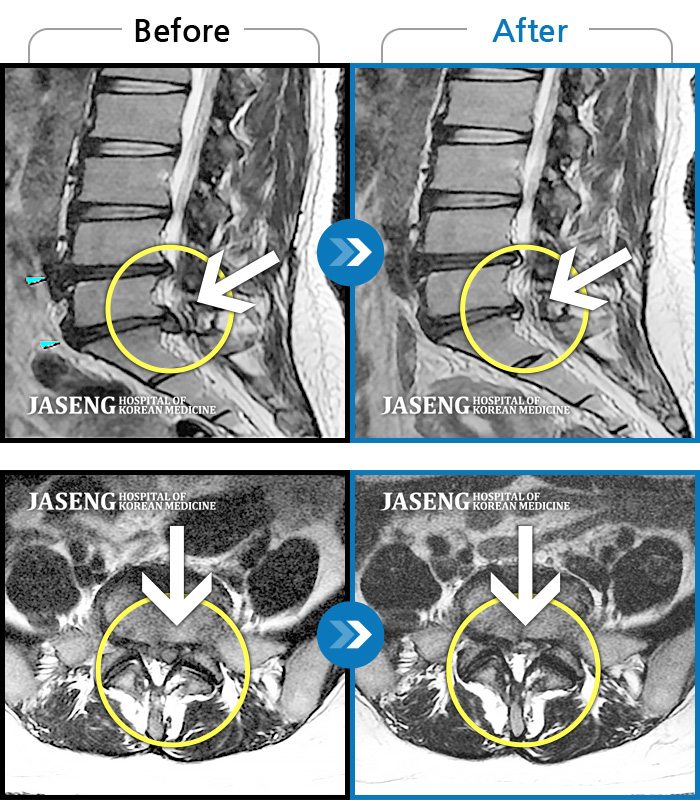

허리디스크

보라매 · 강준규 원장

우측 허리부터 엉치까지 아프고, 다리 저림이 지속적으로 심하게 느껴져요.

촬영시기

2024.04.06 ~ 2025.02.22